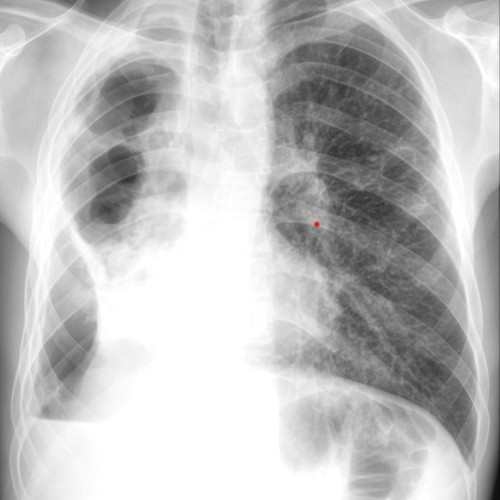

Autoritățile locale au confirmat că actorul a murit din cauze naturale, având probleme cardiace și complicații cauzate de boala Alzheimer. De asemenea, Arakawa a decedat din cauza unei boli rare, sindromul pulmonar cu hantavirus. Se pare că Hackman nu era conștient de moartea soției sale.